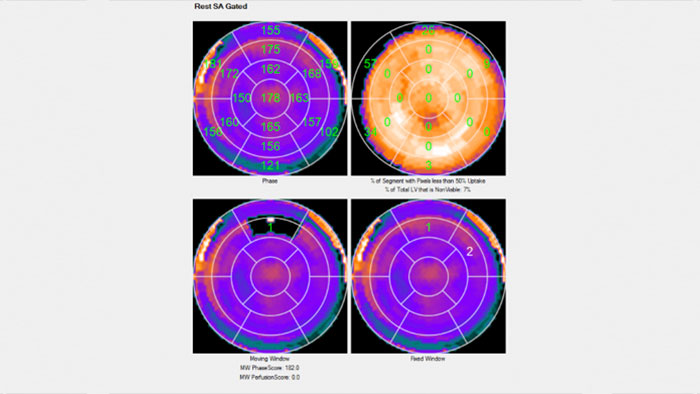

- Emory Cardiac Toolbox (ECTb) SyncTool

-

Emory Cardiac Toolbox (ECTb) SyncTool*

Assess cardiac mechanic dyssynchrony

Emory Cardiac Toolbox (ECTb) SyncTool provides an objective evaluation of left ventricular (LV) dyssynchrony using phase analysis.

Benefits

- Provides additional prognostic information that can be obtained from 3D perfusion images, such as the presence and location of scar tissue.

- Review screen includes phase polar maps, phase histograms, and a summary of systolic wall thickening analysis including peak phase and standard deviation of the phase distribution.

*Emory Cardiac Toolbox, ECTb, HeartFusion, and SyncTool are registered trademarks of Emory University.